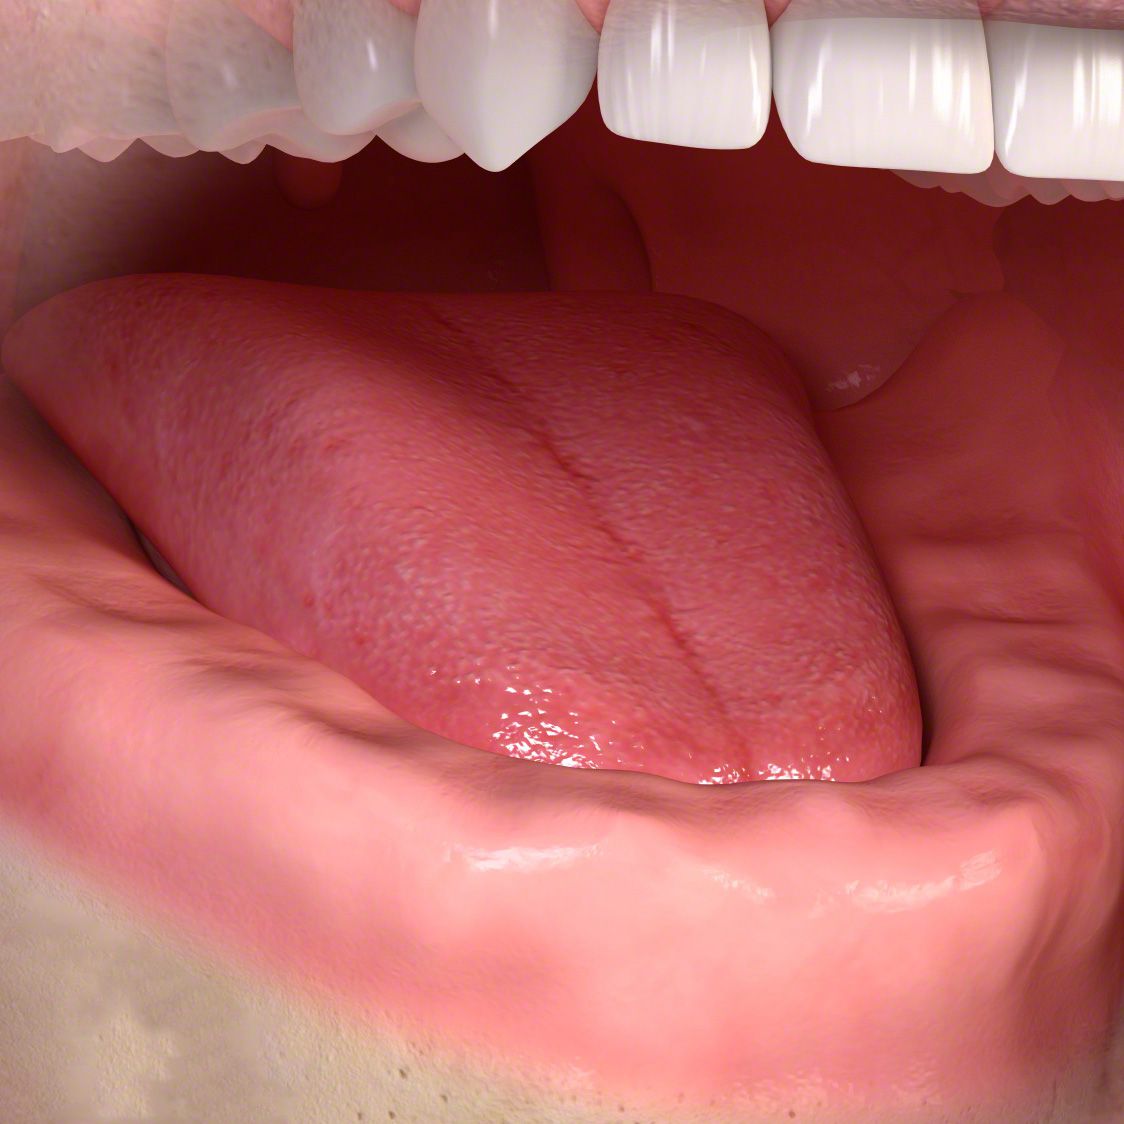

Jeder eigene Zahn ist wertvoll! Wie wertvoll, merkt man erst, wenn er ersetzt werden muss. Im Laufe des Lebens ist das leider oft der Fall. Doch dank Implantaten können wir nicht nur Zahnlücken schließen, sondern sogar kompletten Zahnersatz fest im Mund verankern. Da wackelt nichts mehr!

Die entstandene Lücke kann mit einer künstlichen Zahnwurzel, d.h. mit einem Implantat geschlossen werden. Implantate, meist aus Titan oder Keramik, werden dabei in einem kleinen chirurgischen Eingriff in den Kieferknochen eingesetzt. Nach dem Einheilen tragen sie später den eigentlichen Zahnersatz (Kronen, Brücken, Prothesen).